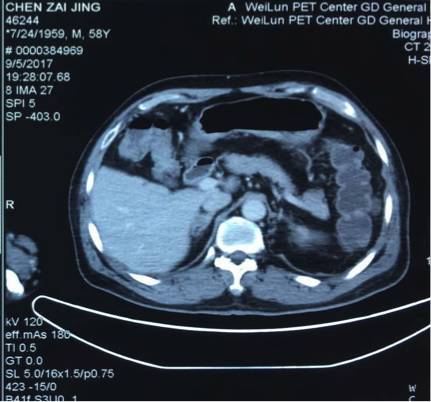

5. 2017-9-5广东省人民医院PET提示:右肺下叶肿物2.8*2.7cm,SUV 22.3,双侧颈部、双侧气管旁、隆突下、食管旁、右侧肺门淋巴结肿大,代谢升高,考虑为转移灶,右侧肾上腺转移灶,具体结果见下图:

7.目前诊断:右下肺肿瘤cT1cN3M1c IVB期(颈部淋巴结、肾上腺)

(准备行经皮肺穿刺活检时图像)

吴一龙医生这个病例的PET-CT有一个特点,右肺下叶的病灶并不大,2.7*2.8cm,但是代谢非常高,高达22.3。这种小病灶高代谢的病灶,在肺癌患者中比较少见。尤其是代谢值大于20但病灶小的情况很少见。我同意谢主任刚的意见,如果该患者没有肾上腺的病灶,我认为诊断可以到此为止。我们可以看到,肺内的病灶有可能是肺内的淋巴结,我们已经对最大的淋巴结进行了活检,为良性病灶。但是,由于该患者多了肾上腺的病灶,用刚才的说法无法解释,肾上腺不属于淋巴系统。结合既往我们遇到的病例,我们现在有两个办法,我认为对于该患者,观察是一个办法,但是如果漏诊会比较麻烦,如果观察一段时间,下次过来复查提示病灶稍增大,我们如何处理?因此我认为现在我们要明确诊断,需要取病理活检,但是是取肺部病灶还是肾上腺的病灶?